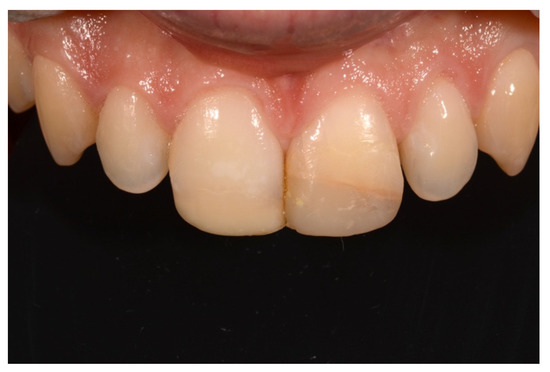

2. Case Presentation